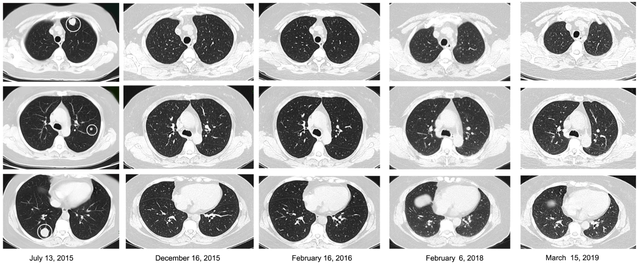

由于肿瘤负荷较低,于是进行TCR基因修饰的细胞治疗。截至2019 年3月15日,该患者已经保持完全缓解状态超过3年!

图片源于细胞死亡与疾病